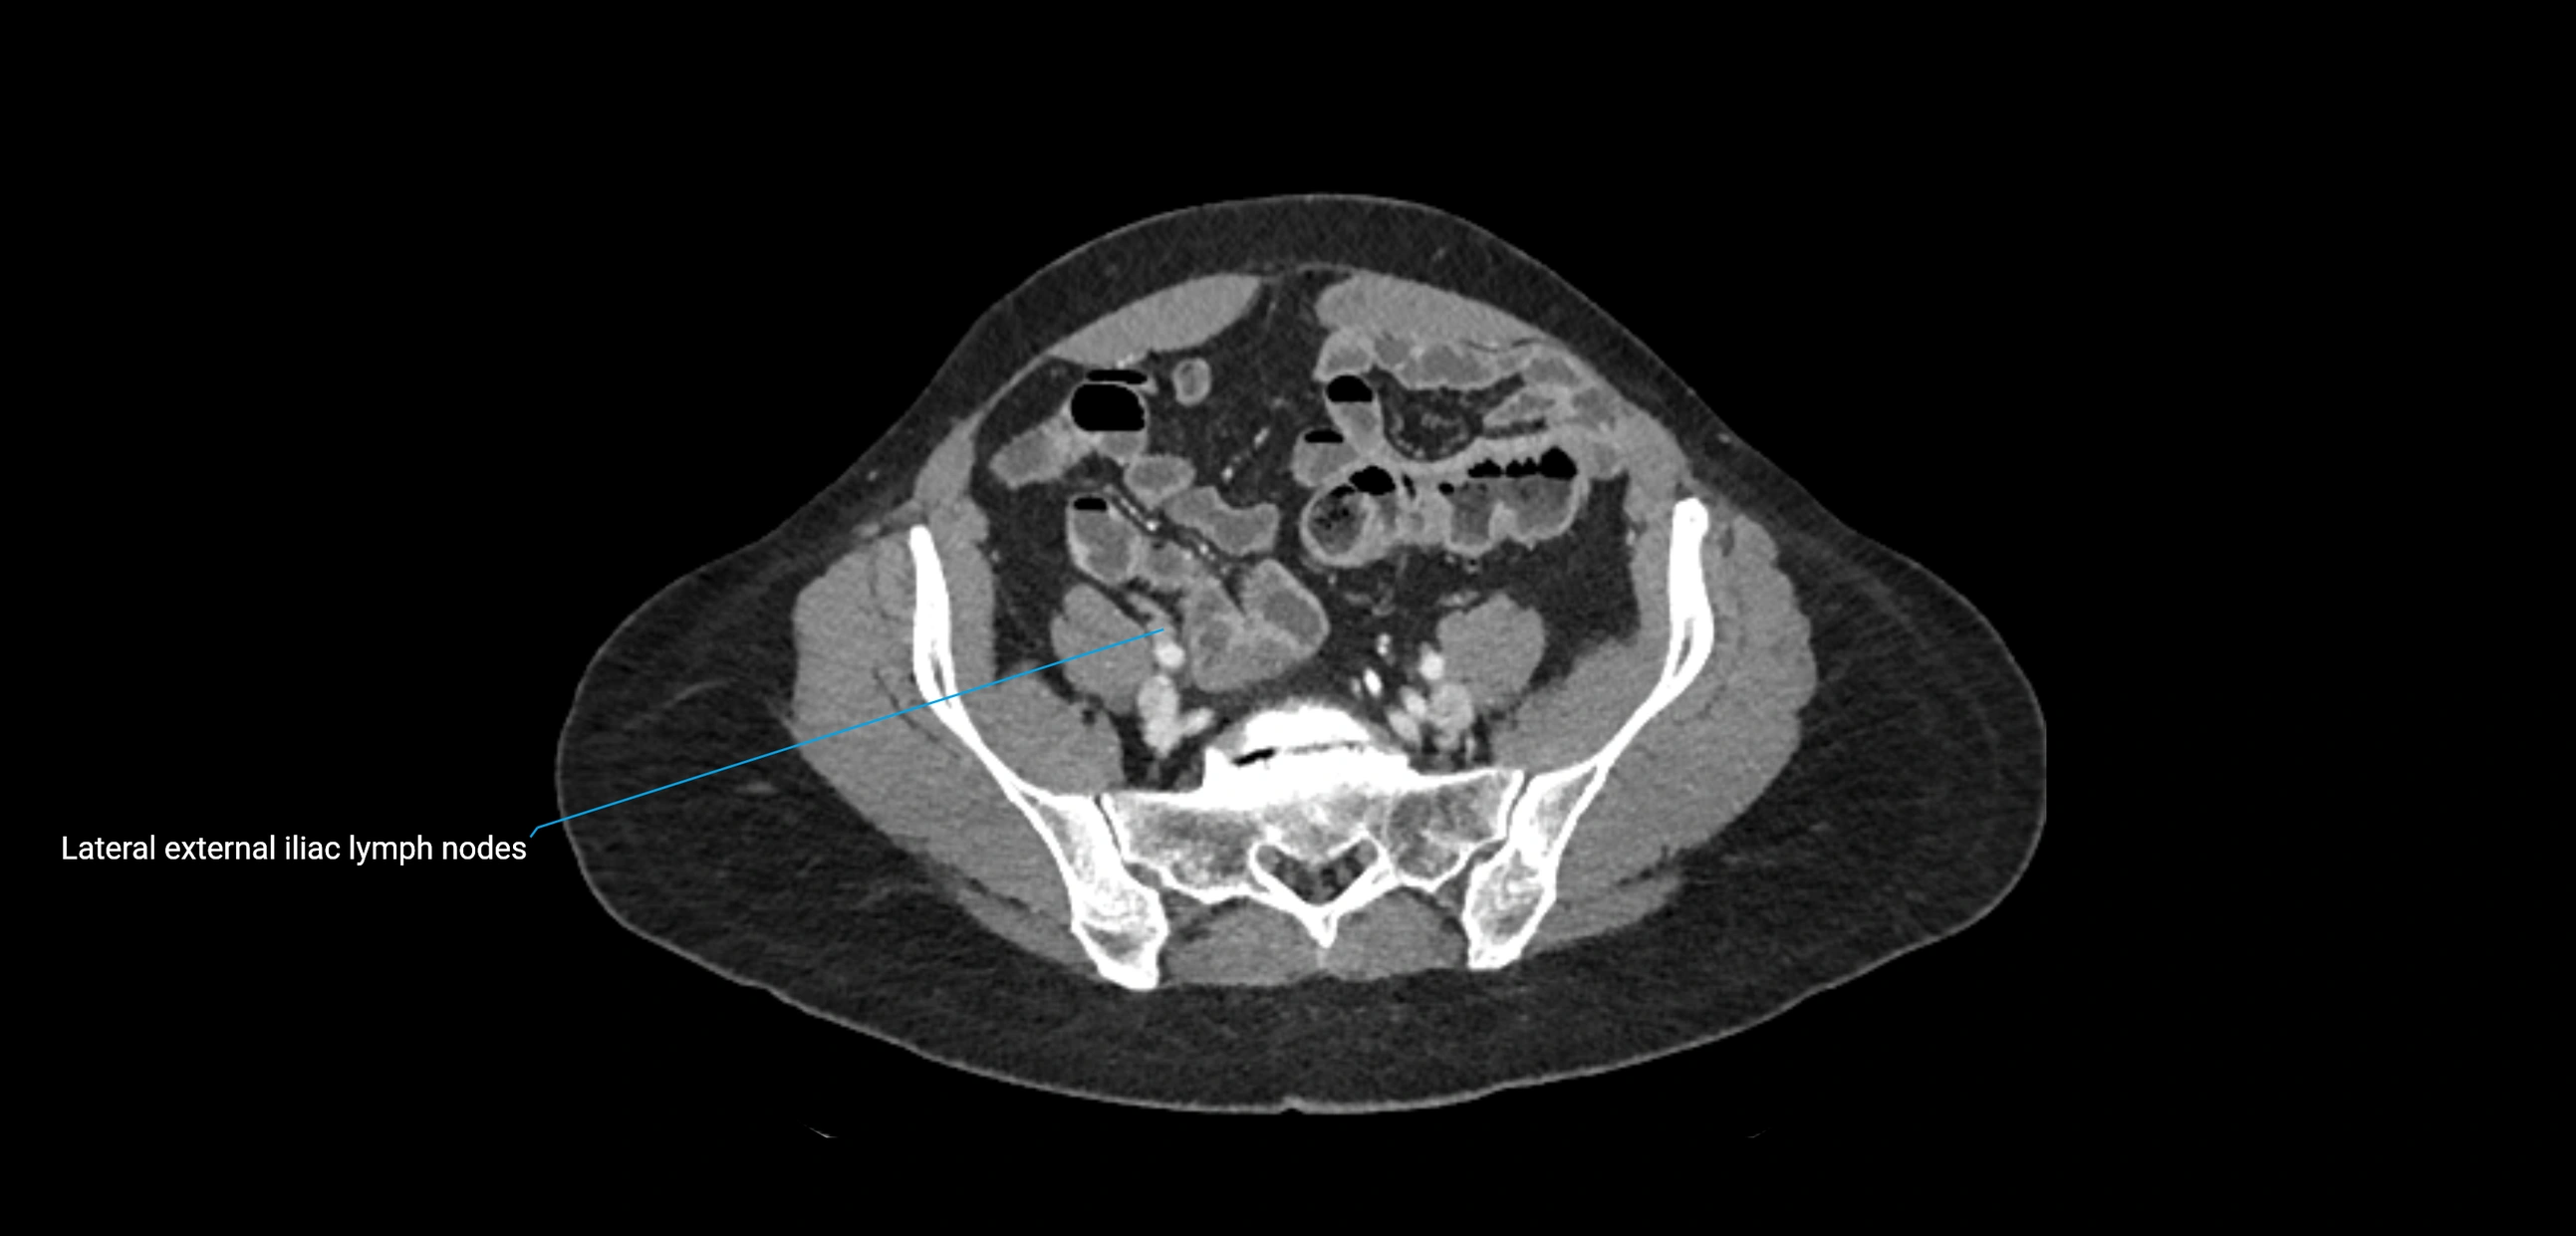

These nodes receive lymph from a wide range of abdominal and pelvic structures. Specifically, they drain lymph from the kidneys, suprarenal glands, gonads (testes/ovaries), uterus, uterine tubes, and pelvic organs, before converging into the lumbar lymphatic trunks, which terminate in the cisterna chyli → thoracic duct.

Clinically, the lateral aortic lymph nodes are critically important in oncology, being involved in the spread of testicular cancer, ovarian cancer, endometrial cancer, cervical cancer, renal malignancies, and retroperitoneal lymphomas. They are also key targets in retroperitoneal lymph node dissection (RPLND) for testicular tumors.

CT Venography (CTV):

• Demonstrates nodal encasement or compression of adjacent vessels (aorta, IVC, renal veins)

• Useful in staging testicular and ovarian malignancies

• Provides 3D reconstructions for retroperitoneal lymph node dissection planning